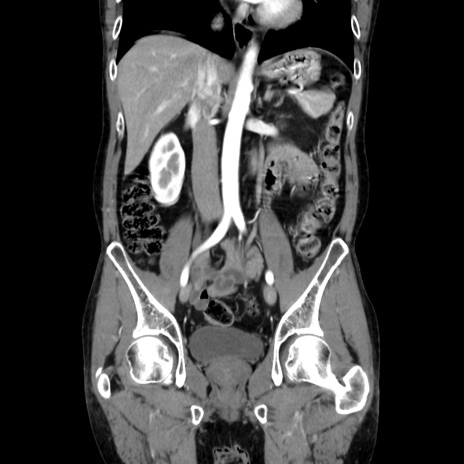

症例37(冠状断像)

【症例】40歳代 男性

【主訴】腹痛

【現病歴】4時間ほど前に電車に乗車中に臍部上より腹痛出現。徐々に増悪し起立困難となり、救急外来受診。生ものは数日食べていない。今朝お雑煮を食べた。

【身体所見】BT 36.8℃、BP 117/84mmHg、HR 91/min、SpO2 97%、苦悶様、腹部:臍上部広範囲圧痛あり、反跳痛±

【データ】WBC 8100、CRP 0.03

横断像